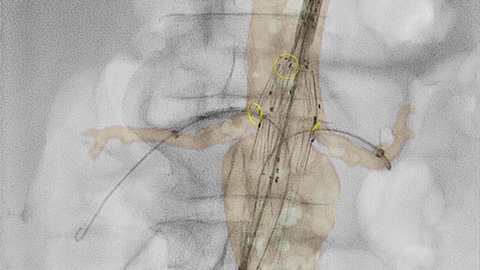

Ofrecemos una gama de herramientas clínicas avanzadas, como VesselNavigator, EchoNavigator y HeartNavigator para la orientación por imágenes 3D en vivo. Nuestra exclusiva Dynamic Coronary Roadmap (hoja de ruta coronaria dinámica) le ayuda a navegar por las arterias tortuosas de manera eficiente y precisa. Cada disciplina quirúrgica puede beneficiarse de herramientas avanzadas de fusión de imágenes que pueden mejorar la confianza, la eficiencia y la precisión durante los procedimientos.

SmartCT* le proporciona imágenes similares a las de la TC lo que le permite hacer mediciones y visualizaciones avanzadas en la pantalla táctil en la mesa, para estudiar el tipo y la extensión de la enfermedad con gran detalle. Las imágenes 3D de SmartCT* pueden ayudar a revelar información no aparente en las imágenes 2D o de la DSA. Esta información adicional puede cambiar el diagnóstico, la planificación del tratamiento o la administración del tratamiento, lo que respalda un mejor resultado para el paciente.17-19

A través de la herramienta del marcador en la pantalla táctil, puede señalar un área de interés en las imágenes 2D. Las marcas se muestran con claridad en la fluoroscopia y las imágenes de referencia, y se escalan y desplazan con la imagen. Esto puede ser útil para marcar una bifurcación, ramas laterales y otros detalles relevantes. Con la herramienta del marcador, no hay necesidad de una aplicación de marcador independiente en sala de intervencionismo.